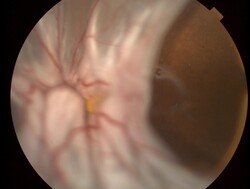

Imágenes

Figura 3: Desprendimiento de retina bulloso superior con gran desgarro temporal.